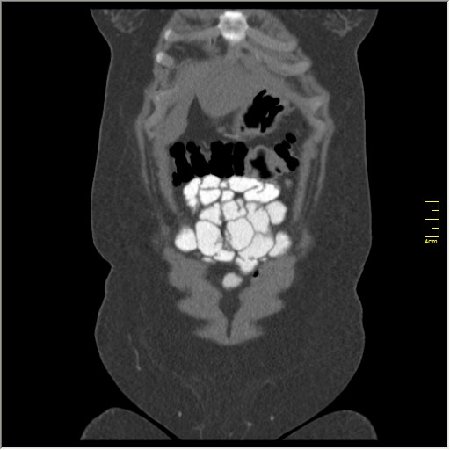

КТ энтерография

Демонстрационные изображение, оцените возможности метода! Толщина среза реконструкции 0.5-1 мм.